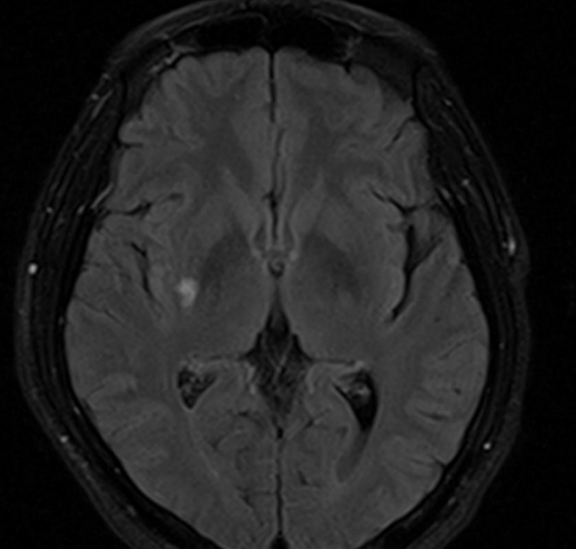

=>lacune 의심 (Clumsy hand syndrome)

==> Rt M1 stenosis

TCD에서 우측의 MCA PV비가  좌측의 40%

RACA를 통한 측부순환 발달해 있음.

O) MRI 에서 우측 BG에 쐐기모양의 old infarction 병변 보임. CTA에서 Rt M1 보다 원위부 혈관이 보이지 않음